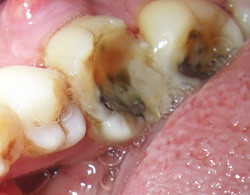

1.歯牙破折

歯冠破折と歯根破折

過剰な咬みあわせやむし歯などで歯の一部が噛み合わせなどの原因で欠けてしまう現象です。

※ 歯牙破折を防ぐには 歯牙破折はむし歯を治療した境目付近によく起きます。さらに歯根破折のほとんどはむし歯などで歯の神経を取った後に起きています。